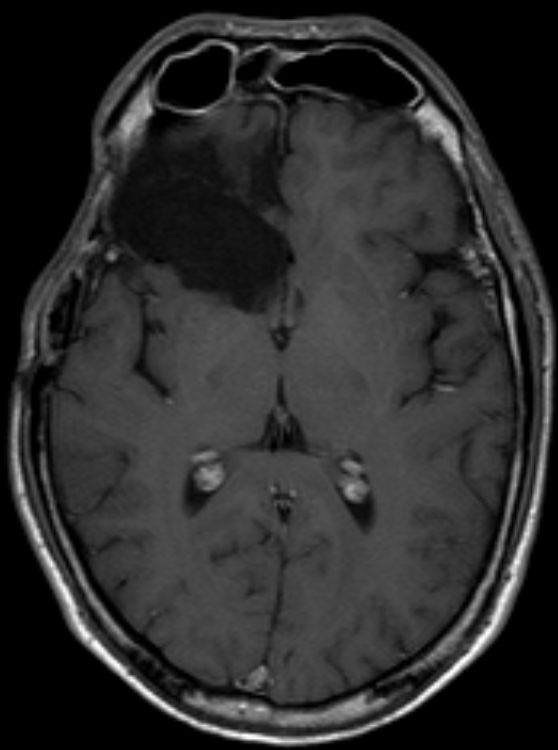

CT |

51-jähriger Mann mit Sehstörung rechts, Kopfschmerz und Schwindel.

Das CT zeigt einen Herd im Splenium corporis callosi links.

Der Tumor erreicht das Hinterhorn.

Stereotaktiosche Punktion: Glioblastoma multiforme.

Eine 2. Läsion im Inselbereich wurde nicht histologisch gesichert.![]() | ||||